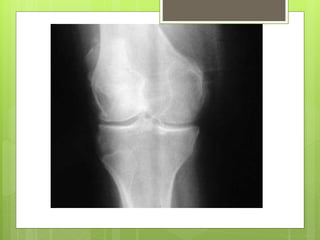

Radiographic changes

Kellgren and Lawrence classification

Radiographic changes Kellgren andLawrence classification

A: A normalknee joint B: Osteophyte formation that has formed at one side of the knee causing malalignment A B